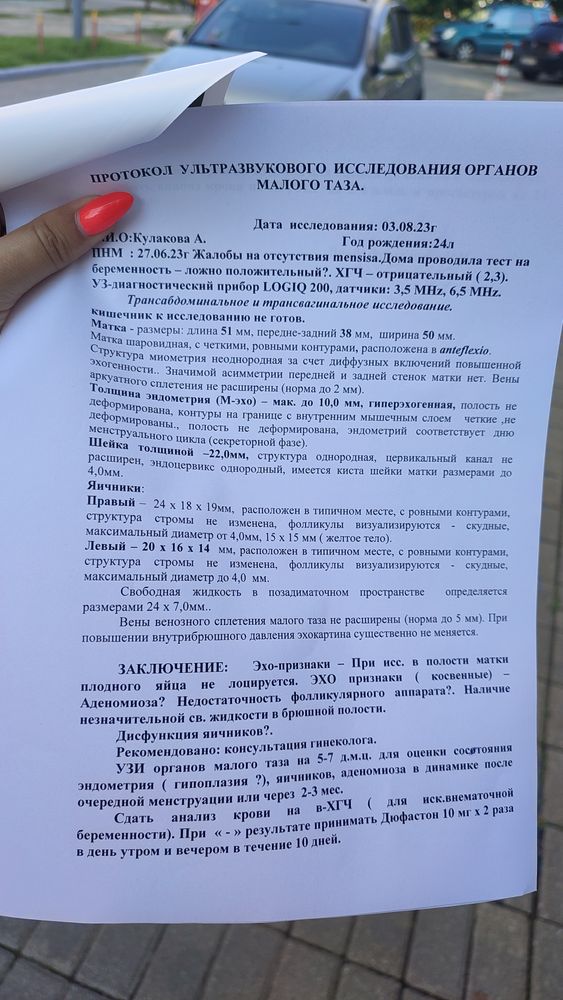

Жёлтое тело сегодня 15 на 15

А по УЗИ овуляция была жёлтое тело 15 на 15

А по УЗИ овуляция была жёлтое тело 15 на 15

А по УЗИ овуляция была жёлтое тело 15 на 15

А по УЗИ овуляция была жёлтое тело 15 на 15

Смородинка, по УЗИ где то в этом районе,а сдавала прогик я получается раньше.

Это сегодня смотрели

Смородинка,

Это сегодня смотрели

Смородинка,